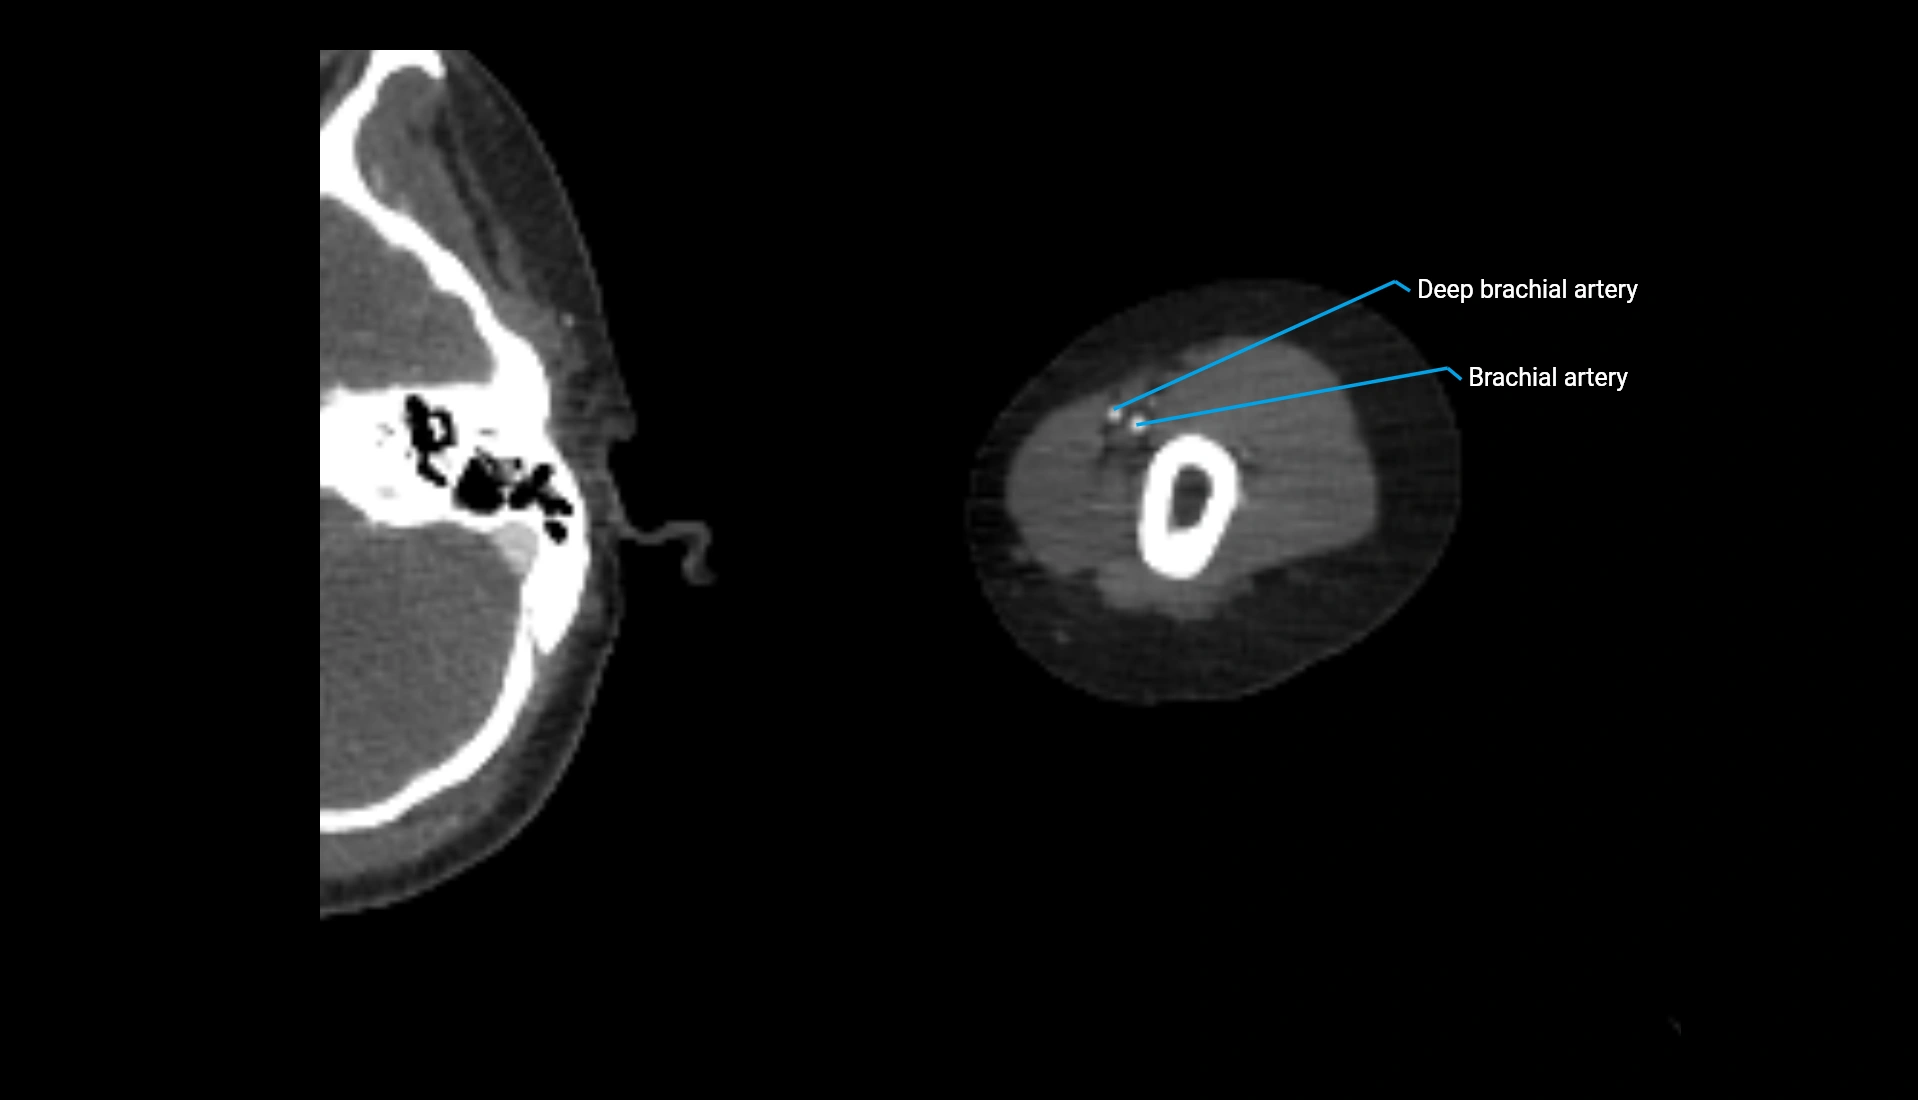

CT Appearance

Non-Contrast CT:

• Cortex: High-density, sharply defined

• Subchondral bone: Dense cancellous matrix

• Articular surface: Smooth concave contour articulating with the capitellum

• Excellent for evaluating bone integrity, alignment, and subtle fractures

Post-Contrast CT:

• Bone: No enhancement

• Joint capsule and synovium: Mild enhancement outlining the joint

• Improves contrast between soft tissues and bony margins

• Useful in detecting subtle joint abnormalities or postoperative changes